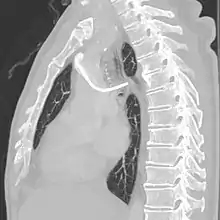

Follow-up chest X-ray after insertion of a port, with a malpositioned tip in the azygos vein.

CT scan of the same patient confirming the position of the port tip in the azygos vein.